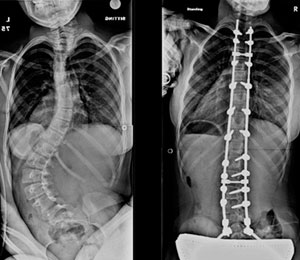

Me diagnosticaron escoliosis cuando tenía 13 años, en el año 2010 y ese mismo año me operaron en el mes de octubre. Al inicio, no me gustó la idea de la operación porque interfería con algunos planes que ya tenía en mente, pero sabía que si quería estar bien, tenía que sacrificarlos porque más importante era mi salud. No muchos doctores saben de esta enfermedad, gracias a Dios conocí al Dr. Cárdenas que fue muy amable y amigable conmigo y me explicó con todo detalle como sería la intervención; así que más que miedo, sentía emoción porque llegara el día.

Después de mi operación, solo estuve internada 4 días. Tengo 11 tornillos en mi columna y ya llevo 5 años de operada; vivo una vida normal y soy feliz.